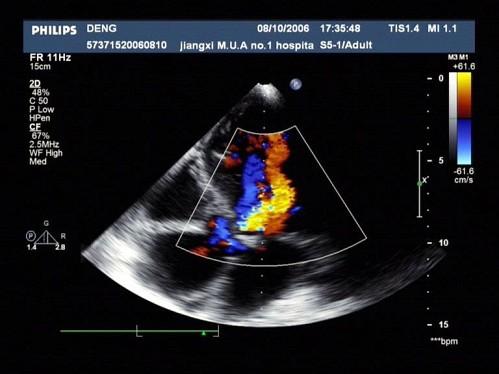

彩超跟B超的区别,是在其基础上增加了多普勒功能。多普勒功能指的是通过运用相关技术,将获得的血流信号处理并叠加在B超图像上,使我们看到红色或蓝色的血流,让我们判断血液流动的情况。

就像我们平时对着一根水管拍照,单纯使用B超的话,我们只能在照片里看到它的外形;若加上多普勒功能,我们就能看到水管里的水是往哪边流了。